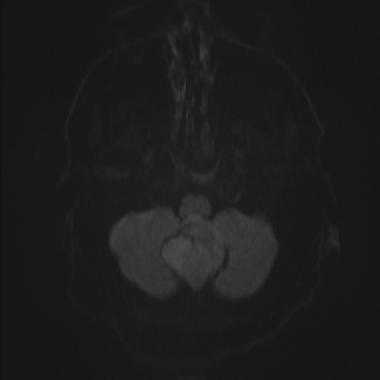

Были сделаны различные выводы касательно роли диффузионно-взвешенной МРТ. Измеряемый коэффициент диффузии (ИКД) для высокодифференцированных опухолей обычно оказывался ниже по сравнению с окружающей тканью головного мозга. Некоторые исследования показали схожую тенденцию в случае менингиом, но по данным других исследований значения ИКД для 1-й и 2-й степеней злокачественности статистически достоверно не различались.

Менингиома задней черепной ямки: диффузионно-взвешенное МР-изображение (DWI). Сигнал умеренно повышен, что соответствует умеренному ограничению диффузии.

Было показано, что значение измеряемого коэффициента диффузии (ИКД), равное 0,85, при использовании диффузионно-взвешенной МРТ позволяет отдифференцировать менингиому 1-й степени злокачественности от опухолей 2-й и 3-й степеней злокачественности. В исследовании на 389 пациентах 1-я степень злокачественности по ВОЗ была диагностирована в 271 случае (69,7%), 2-я степень - в 103 случаях (26,5%), 3-я степень - у 15 больных (3,9%).